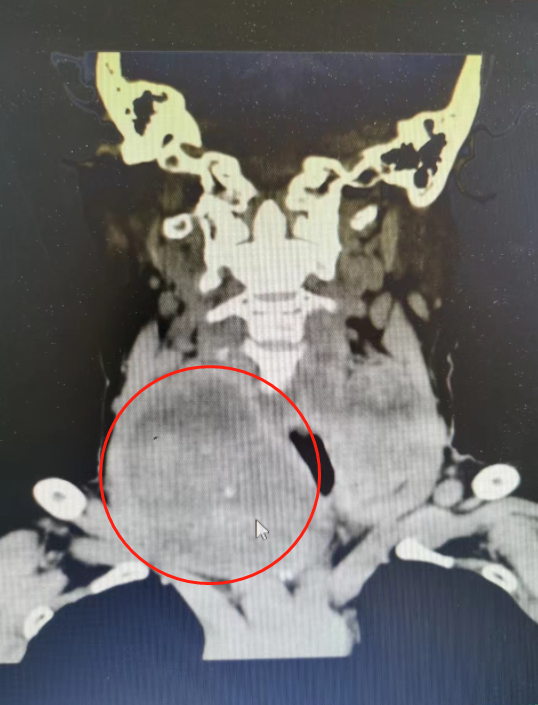

近日,郁南县人民医院普外科成功帮助患者切除颈部肿物(约10+cm),颈部切口约4cm。

患者女,73岁,因“发现颈部肿物40+年”入院,入院后完善相关检查,在排除手术禁忌症后,在全麻下行双侧甲状腺肿物次全切除术。

术中患者颈部肿物巨大,导致术野难以暴露,这无疑给手术增加不少难度。

在南方医科大学第三附属医院普外科帮扶专家于晓园教授指导下,郁南县人民医院普外科林俊双主任小心翼翼分离甲状各级动静脉及逐一结扎,同时保护好喉返神经、喉上神经、甲状腺旁腺。手术团队助手配合林主任拉开术口,暴露术野。

历经3个小时不懈努力,普外科手术团队成功切除颈部巨大肿物,术程顺利。